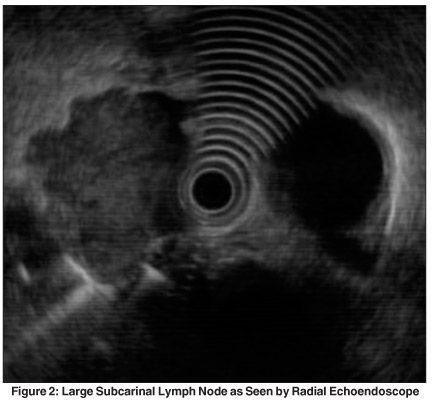

EUS-FNA can be performed in an outpatient setting. The technique, procedure time, and complication rate is similar to that of standard esophagogastroduodenoscopy (EGD). FNA is performed under direct visualization using a flexible linear-array echoendoscope (Figures 1 and 2). The surrounding blood vessels can be visualized by Doppler sonography. Patients can be typically discharged after 30 minutes of postprocedural observation. Reports of bleeding, infection, and pneumothorax are extremely rare. An attendant cytotechnician or cytopathologist increases the yield and accuracy of EUS-FNA.